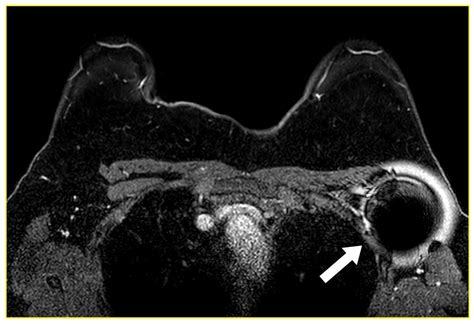

Image-Guided Localization Techniques for Metastatic Axillary Lymph ...